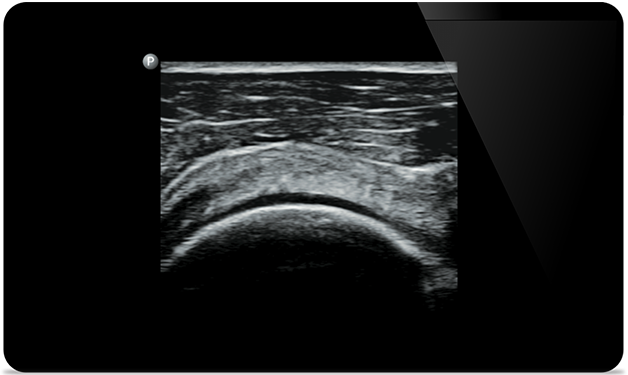

Padstatic case example image

Get the clarity of larger ultrasound systems with Lumify

Get the clarity of larger

ultrasound systems

with Lumify

SonoCT reinforces real tissue imaging while eliminating random artifacts. This technology produces images superior to conventional imaging in up to 94% of patients.